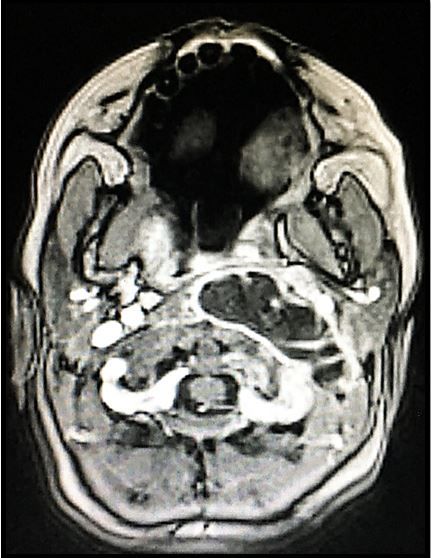

1. What does the image show?

1. The case image shows: A retropharyngeal abscess, mostly left of midline.

For more on retropharyngeal abscess, see sample page in Figure 2, at right; click image to enlarge, then review highlighted area.

Retropharyngeal abscess (RPA) typically presents with fever, sore throat, and a stiff neck. Headache and/or neck pain may also be present and may be worse than the sore throat. Rarely, a sore throat is absent.

Physical examination may show neck stiffness, but unlike with meningitis, stiffness often occurs with rotation or extension more commonly than with flexion. In severe cases, stridor from airway compromise may occur as may concerning vital signs related to sepsis.

The diagnosis is typically made with a lateral neck x-ray. CT scan with contrast is more sensitive and can also be useful for surgical consultants in tailoring treatment. Treatment should be initiated with IV antibiotics that cover staph, strep, and anaerobes. Surgery is indicated for severe cases or for those that do not respond to IV antibiotics.